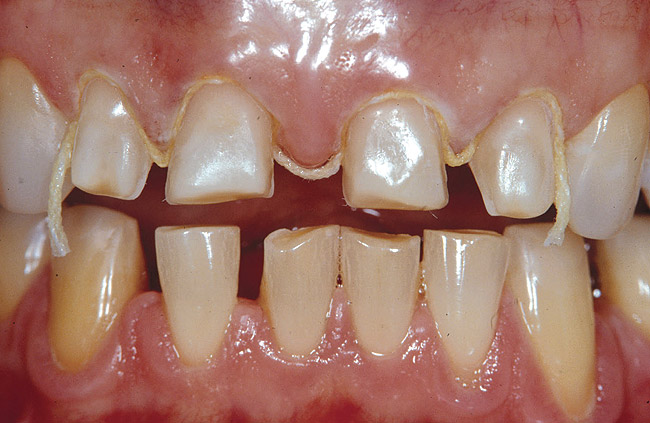

Figure 1c  Clinical view just before the final impression. Note the immediately sealed facial dentin surfaces (smooth texture  of sealed dentin on all four incisors), which is a key element in the long-term success of indirect bonded restorations. The palatal surfaces  were left intact and unprepared.

Figure 1c

Figure 2a  Immediate dentin sealing is particularly  challenging when dealing with dentin  margins in veneer preparations for anterior  teeth (red rectangle shows the schematic  cross-sectional view of gingival dentin margins  in images C, E, G, I, J, L-N, and P-S).

Figure 2a

Figure 2b  Clinical situation during preparation of the  eroded teeth. Existing restorations, as well  as severe initial erosion and wear, led to the  realization of a shoulder facial preparation.

Figure 2b

Figure 2c  A marked gingival chamfer always facilitates  the application of the dentin bonding  agent. Immediate dentin bonding would not  be possible in the presence of a traditional  light chamfer because the adhesive layer  tends to pull over the margin, creating a feather-  edge finish line and insufficient margin  definition.

Figure 2c